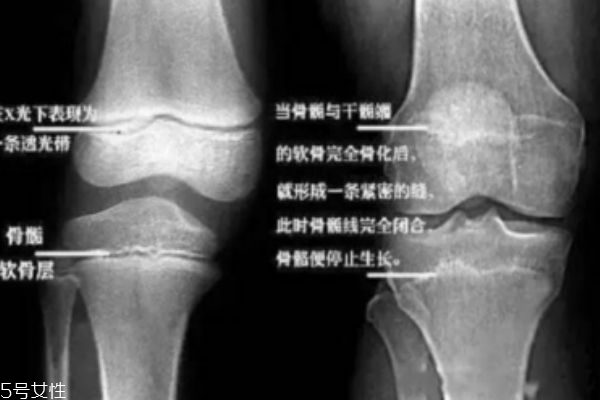

• 1、取决于骨骺线(记住它,它是你长高的关键)是否闭合。

4、人在刚出生时,长骨的骨干大部分已经骨化,但肢长骨的两端还有未骨化的骨骺。

5、骨骺和骨干之间有层软骨层,医学上称之为骺软骨,即骺板,也叫骨骺线。

6、当骺板不断变薄,第三消失,也就是骨骺和骨干完全闭合时,就完成了骨的发育。

7、自此,人就不能再长高了……不能再长高了……长高了……我猜你更想问:怎么知道自己的骨骺线闭合了没呀?很简单,去医院给膝关节拍张X光片就清楚了。

8、骨骺线还透亮透亮的?恭喜你!你还能再抢救下。